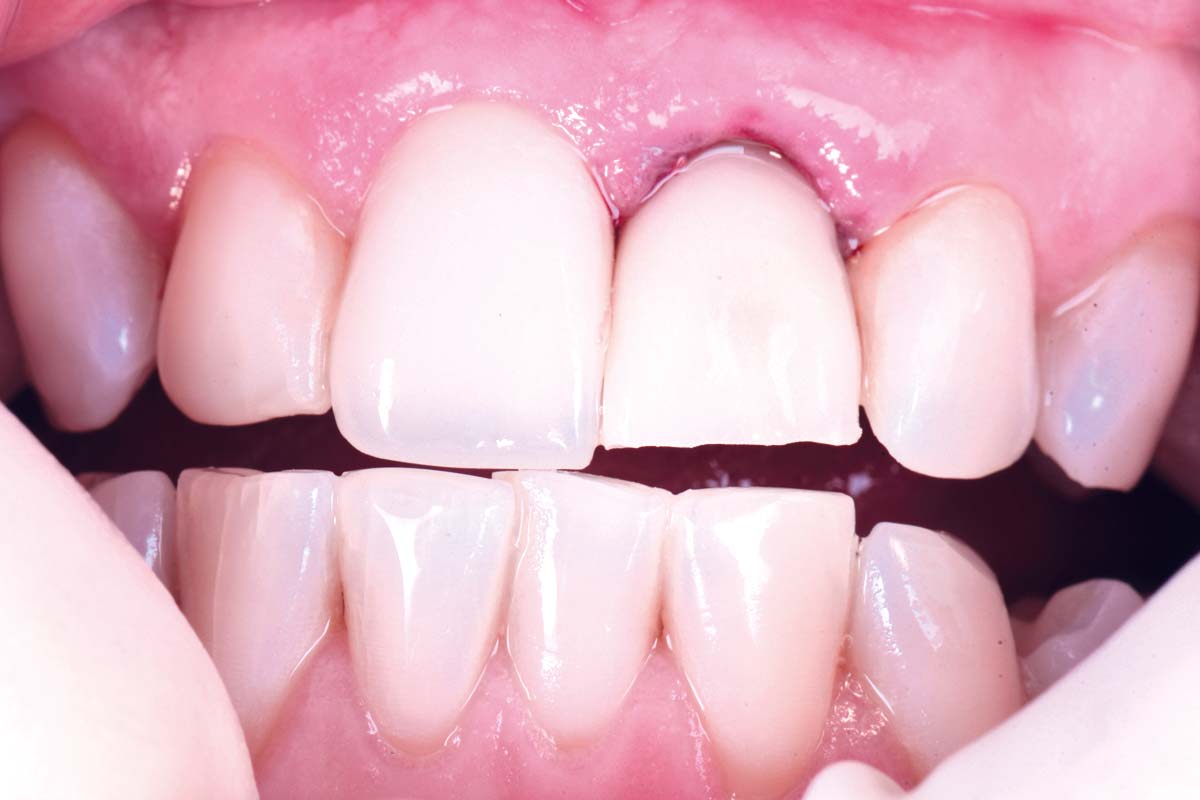

cerabone® and mucoderm® for immediacy in esthetic zone -Dr. M Motta

Initial view of the case. Discoloration of 1.1 and mild class I gingival recession